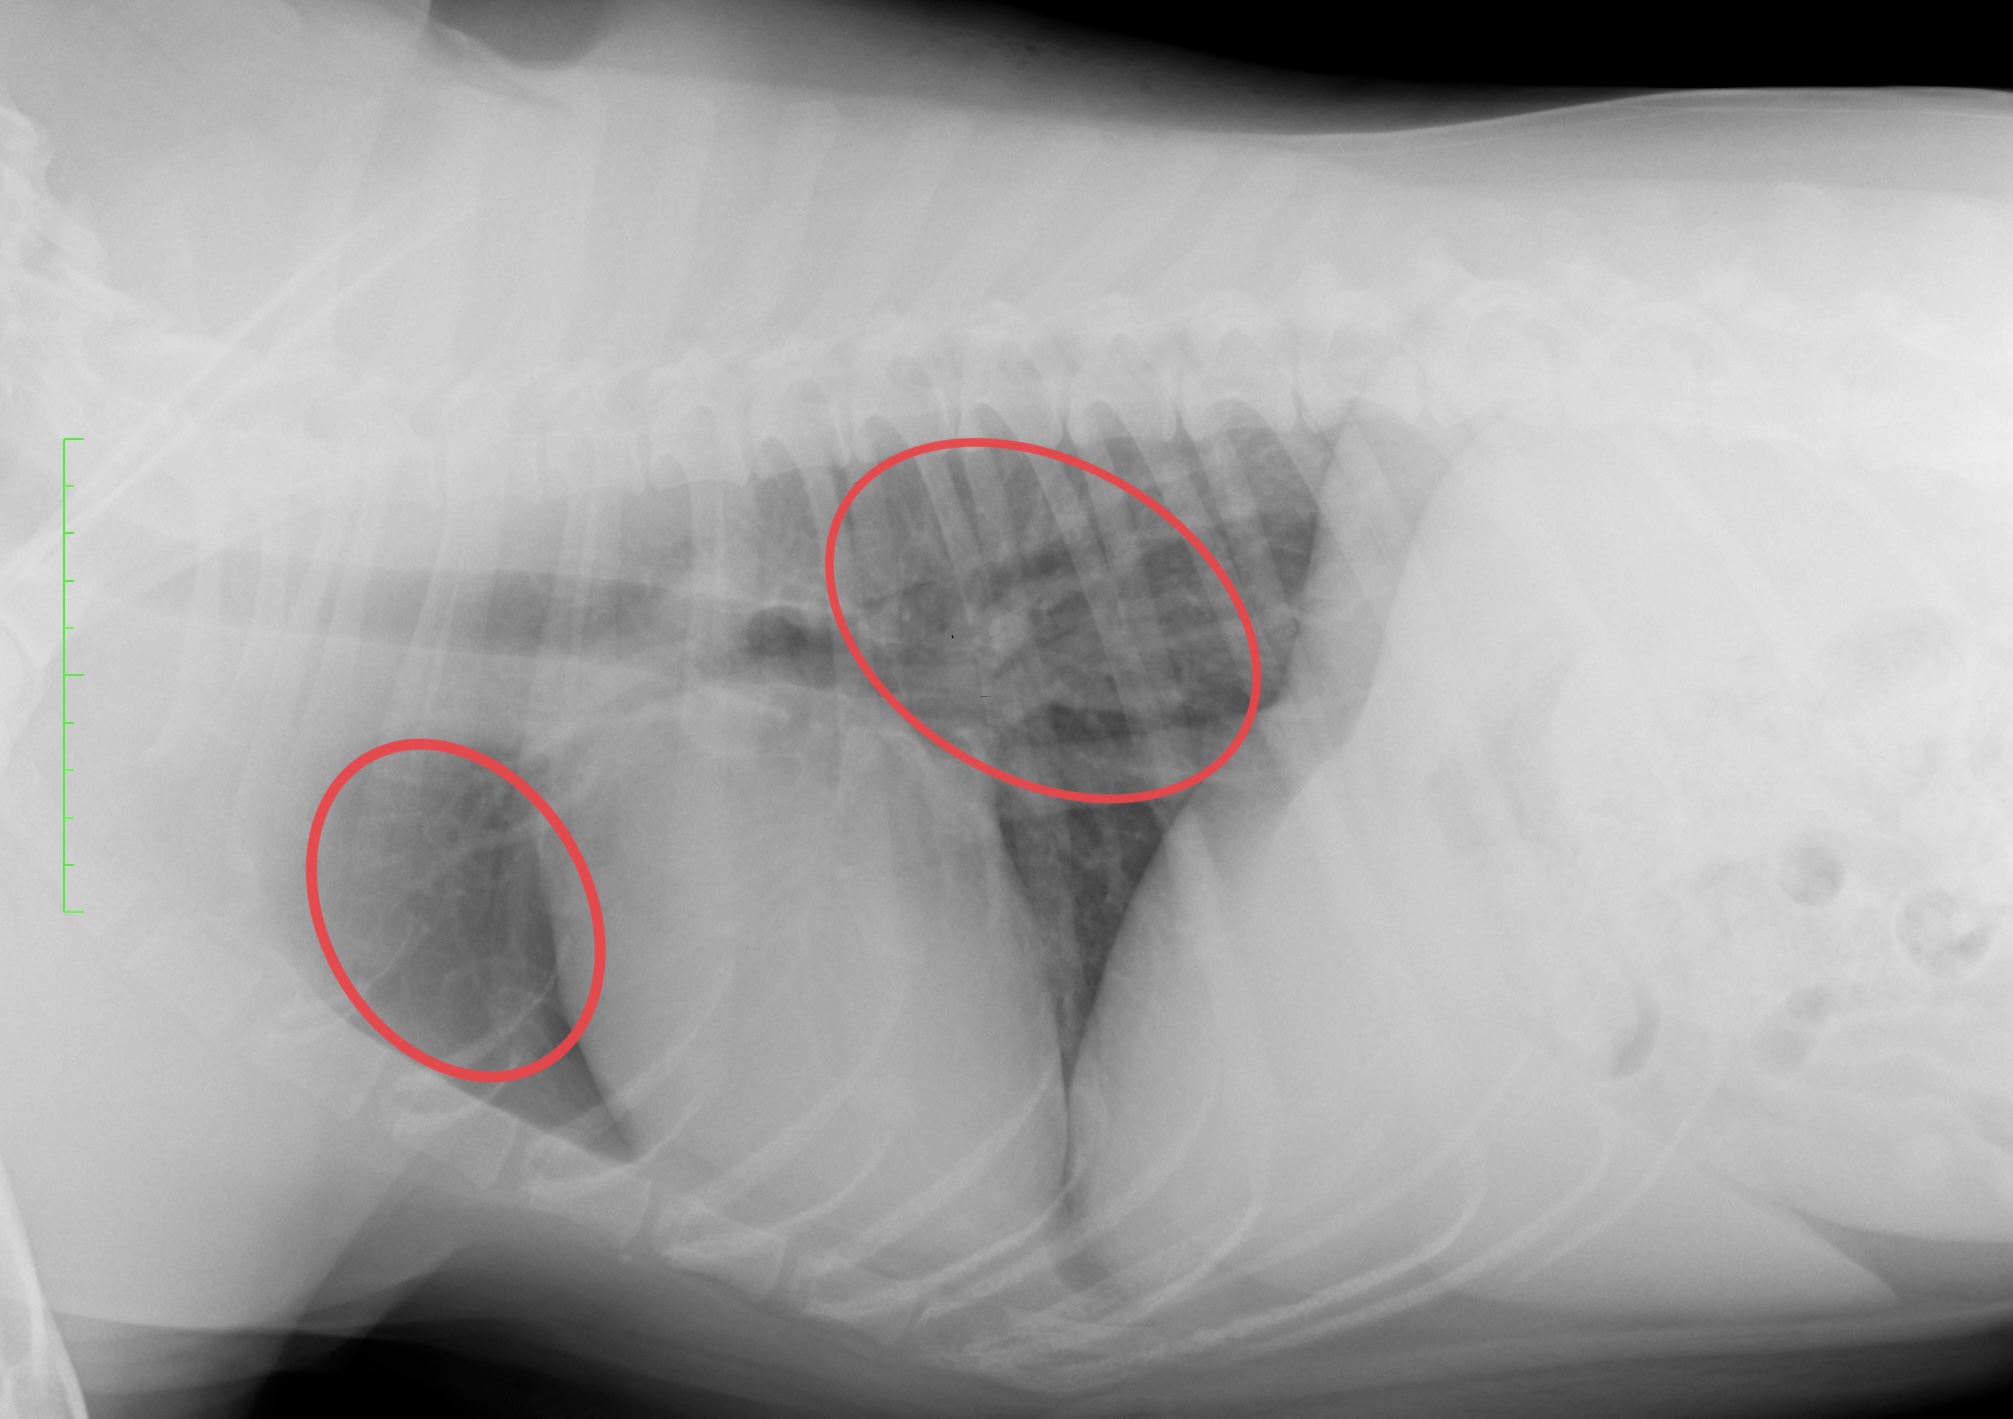

整形外科の雑誌であるVeterinary and Comparative Orthopaedics and Traumatologyに磯野の論文である「Tibial Torsion Malalignment in Small Dogs with Medial Patellar Luxation」が掲載されました。パテラ内方脱臼に対し、脛骨粗面と足根骨の捩れが関与しているをことを示し、その指標の一つを提言した内容になります。ご興味ある方はご覧ください。